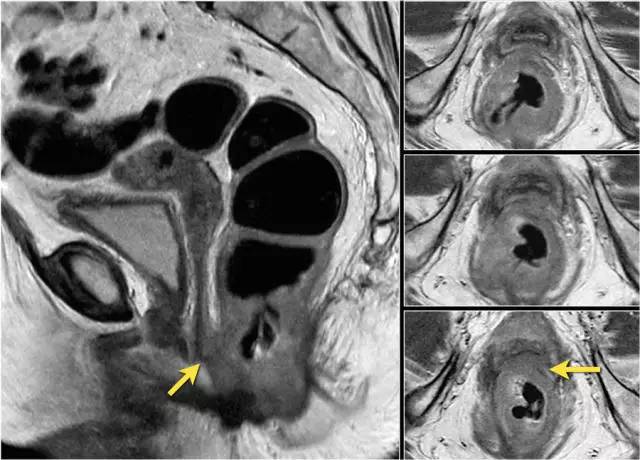

图 16 在矢状 T2W 图像上,直肠和阴道后壁之间有脂肪平面的损失。在轴向图像上,看到肿瘤的相对低的信号强度延伸到阴道的后壁(箭头)

以下 5 幅图例请连续观看:

图 17~21 肿瘤的低信号强度延伸到阴道的后壁(箭头)